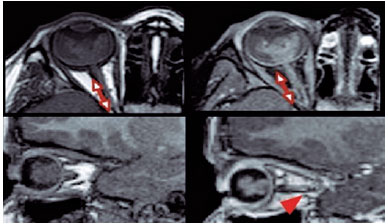

The lesion size was evaluated on the longer axis at T1WI post-contrast (gadolinium) sequences. On MRI, retinoblastoma was considered when the lesion had moderately higher signal intensity on T1WI and lower signal intensity on T2WI in comparison with the vitreous body. Other imaging signs included globe deformation, increased globe size, and reduced anterior chamber and buphtalmia (Figure 1).

Optic nerve involvement was considered when there was thickening, irregular contour, and abnormal enhancement of the optical nerve or discontinuity of the enhancement of the linear choroid-retinal complex. The optic nerve was divided into prelaminar, laminar, and post-laminar segments by the cribriform plate. MRI findings of post-laminar optic nerve infiltration include focal optic nerve enhancement (Figure 2).